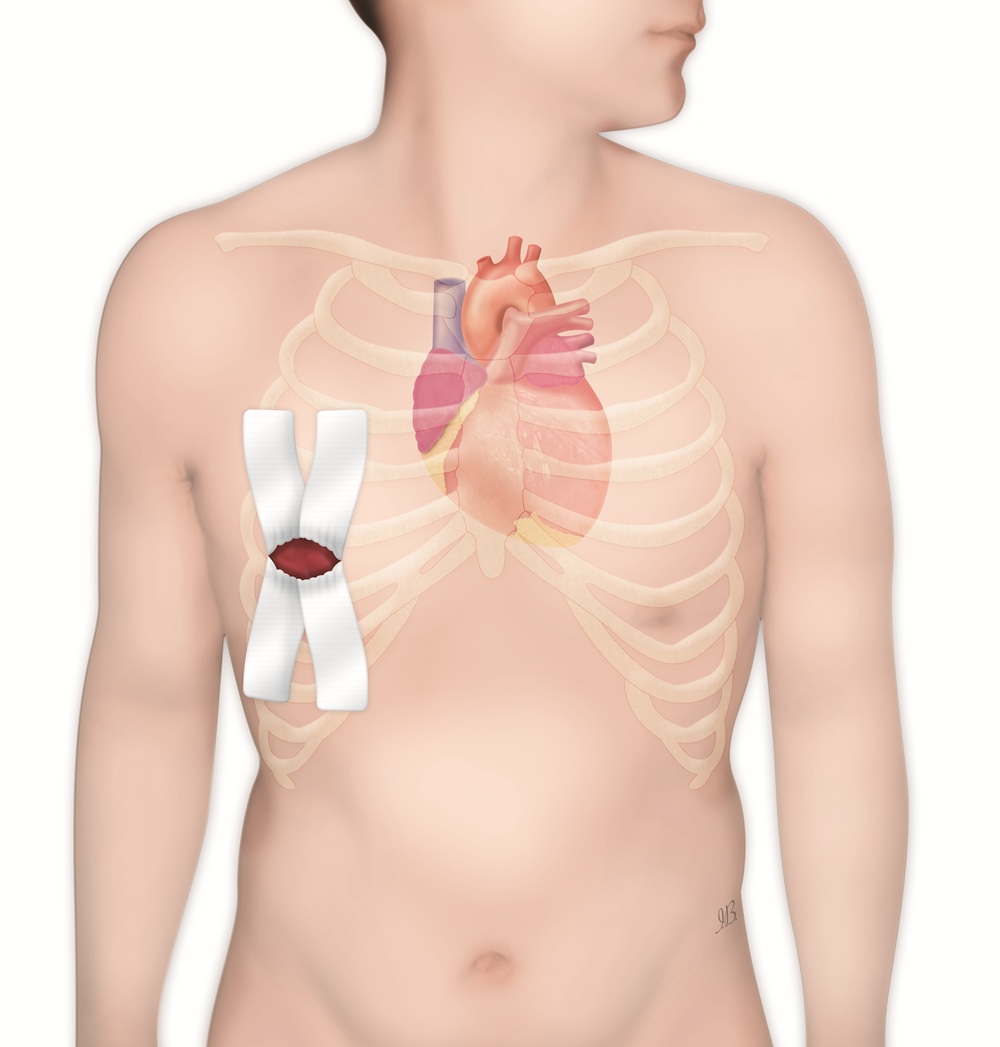

Il mixoma è il tumore cardiaco primitivo più frequente (40%-60% dei casi), con un’incidenza di 5 casi ogni 10mila persone, e che nelle donne è di 3 volte maggiore rispetto agli uomini (MSD Manuals). Si definisce benigno perché non si diffonde ad altri organi, ovvero non dà metastasi. Ma dal punto di vista clinico si comporta in modo “maligno”: può crescere e peggiorare l’ostruzione del flusso sanguigno fino a bloccare il passaggio del sangue, causare embolie ed eventi acuti gravi (ictus, ischemia di organi o arti) e, nei casi peggiori di occlusione acuta della valvola mitrale, anche provocare la morte improvvisa. L’intervento in questo caso è considerato urgente e risolutivo, perché l’asportazione completa porta alla guarigione e riduce al minimo il rischio di recidiva.

“La rimozione di un mixoma atriale sinistro tramite minitoracotomia è complessa per diversi motivi – spiega il prof. Ricci –: il tumore si colloca infatti in una sede delicata, vicino al setto interatriale, a contatto con valvole e vasi, quindi serve estrema precisione. Per questo impieghiamo la chirurgia mininvasiva operando con un accesso ridotto rispetto alla sternotomia tradizionale. Il chirurgo lavora in uno spazio limitato ma con una visibilità migliorata, nonostante ridotti margini di manovra, grazie all’utilizzo di una specifica telecamera (videoscopia). Inoltre, si rende necessario collegare il paziente alla macchina cuore-polmone in circolazione extracorporea, operazione che richiede tecnica ed esperienza. Infine, vi è il rischio di frammentazione del tumore che va invece rimosso integro, evitando che frammenti si stacchino causando embolie”.